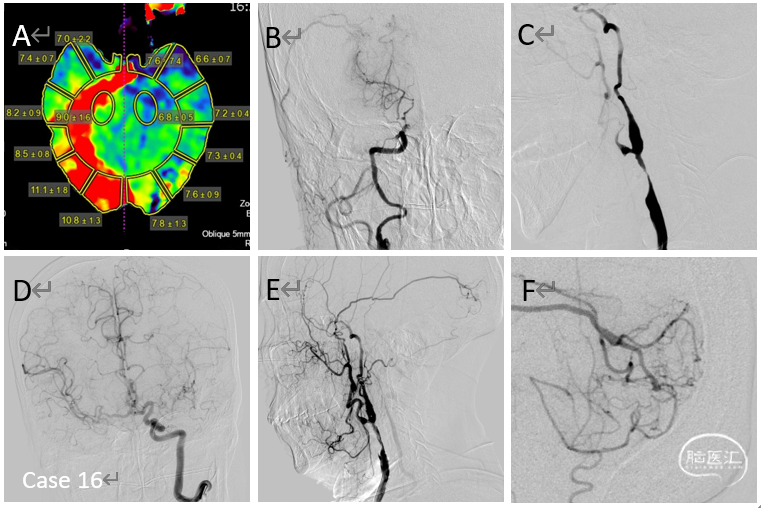

病例16

多发狭窄、闭塞、闭塞前病变,介入似乎没有啥可做的工作。重新DSA评估后发现颈外到颅内新的天然代偿通道,给予右侧颈总动脉狭窄球囊扩张术,术后脑膜中动脉后支向颅内的血供范围明显增加。术后患者自诉:头不晕了,眼睛看东西也清楚了,脑袋也轻松通透了。